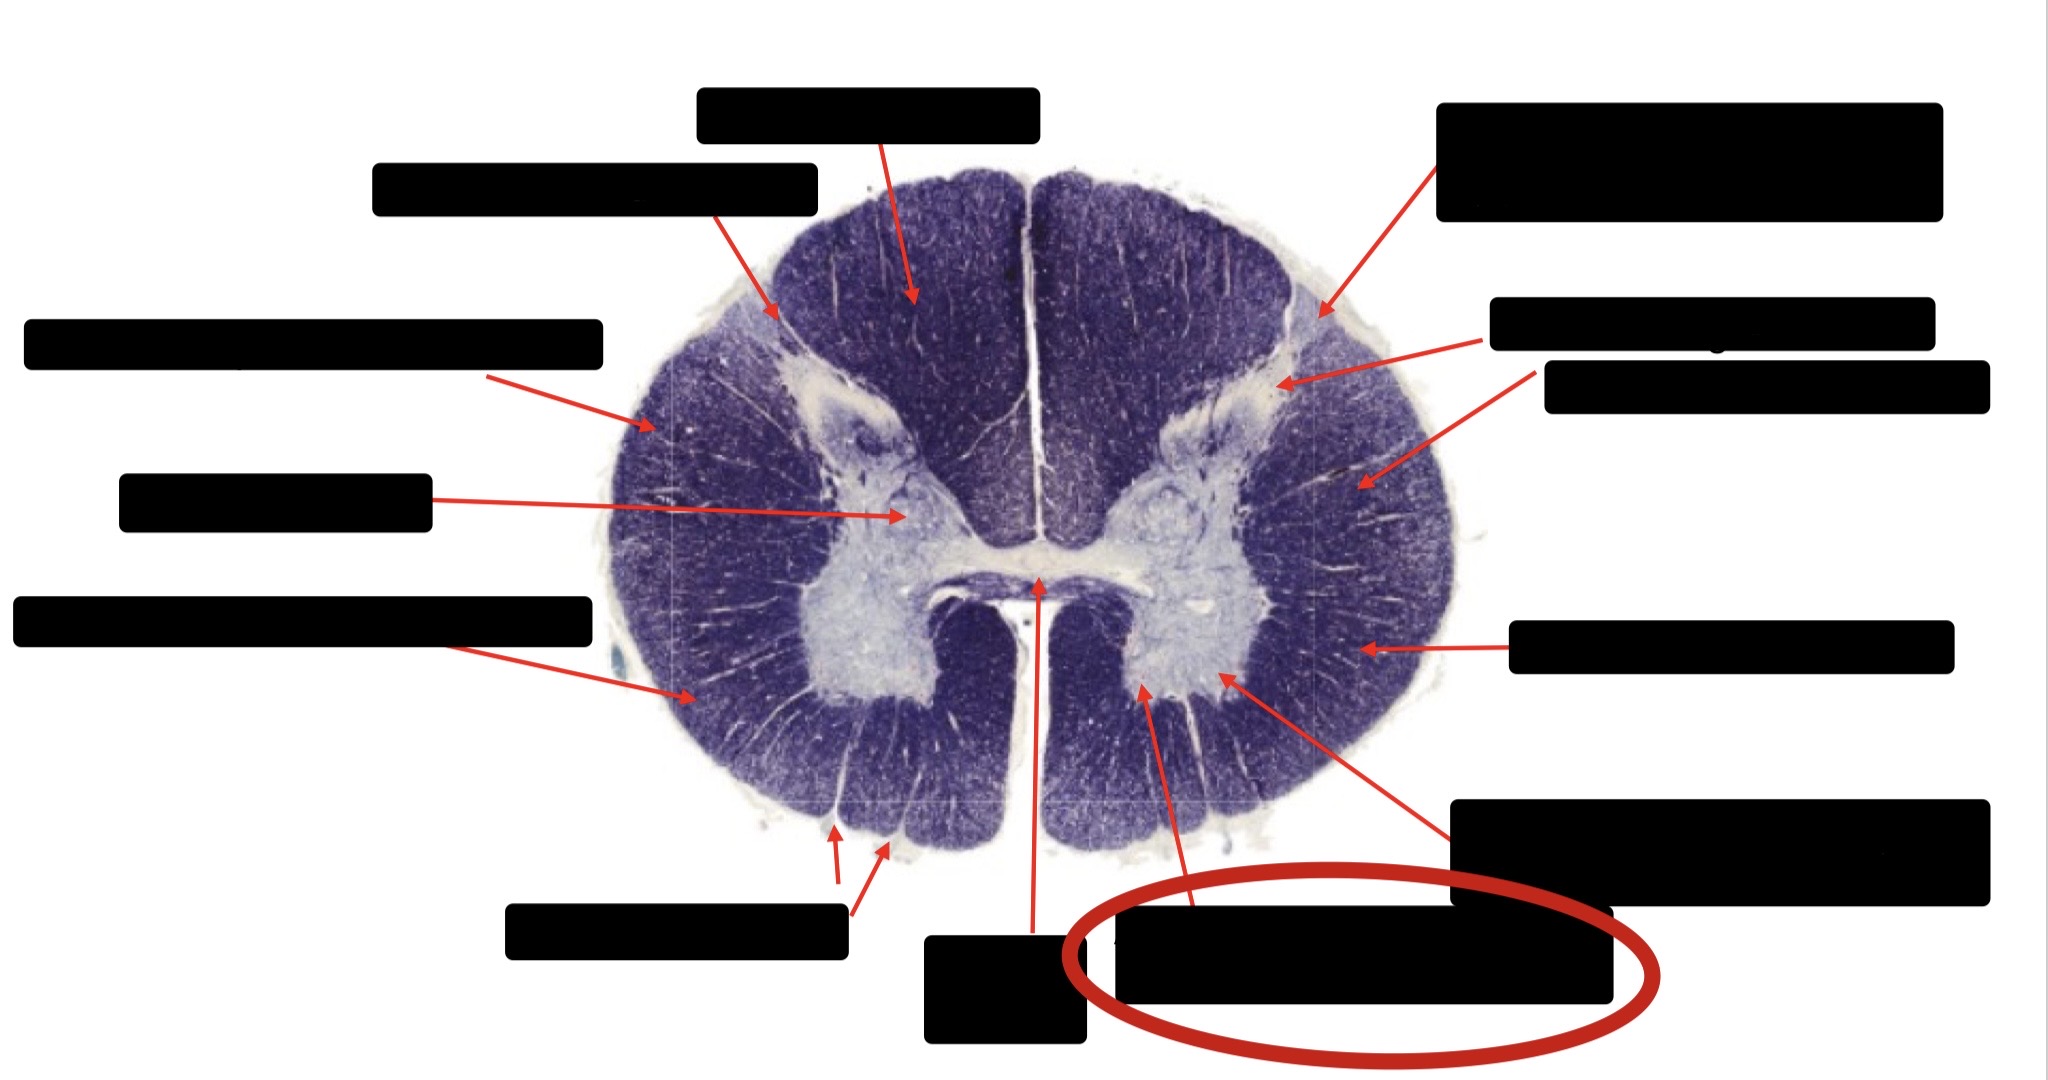

Dorsal Rootlet

Posterior Spinocerebellar Tract

Lateral Corticospinal Tract

Anterior Spinocerebellar Tract

Spinothalmic Tract

Central Canal

Anterior Corticospinal Tract

Posterior Column (Fasciculus Gracilis)

Posterior Column (Fasciculus Cuneatus)

Substantia Gelatinosa

Accessory Nerve Fibers

Anterior Horn Motor Fibers (Accessory Muscles)

Anterior Horn Motor Fibers (Proximal Muscles)

Ventral Root Fibers

Anterior Horn Motors Neurons (Proximal Muscles)

Posterior Columns (Joint Position, Vibration, Pressure)

Fasciculus Cuneatus

Fasciculus Gracilis

Dorsal Root

Dorsal Spinocerebellar Tract

Ventral Spinocerebellar Tract

Lateral Spinocerebellar Tract (Pain & Temperature)

Ventral Root

Anterior Horn (Motor Neurons)

Distal Limb Movements

Lateral Corticospinal (Pyramidal Tract)

Rubrospinal Tract

Axial & Proximal Limb Movements

Lateral Reticulospinal Tract

Vestibulospinal Tract

Ventral Reticulospinal Tract

Tectospinal Tract

Ventral Spinthalamic Tract (Pressure Touch - Minor Role)

Ventral (Uncrossed) Corticospinal Tract (Distal Limb Movements - Minor Role)